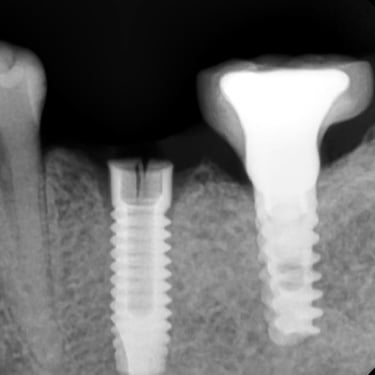

Pérdida de múltiples dientes

La pérdida de múltiples dientes es la ausencia de varios dientes que puede ser resultado de caries, enfermedades periodontales o traumatismos.

Los pacientes notan varios espacios vacíos en su boca, lo que afecta su capacidad para masticar y hablar adecuadamente.

El tratamiento incluye la colocación de varios implantes dentales para restaurar la función y la estética.